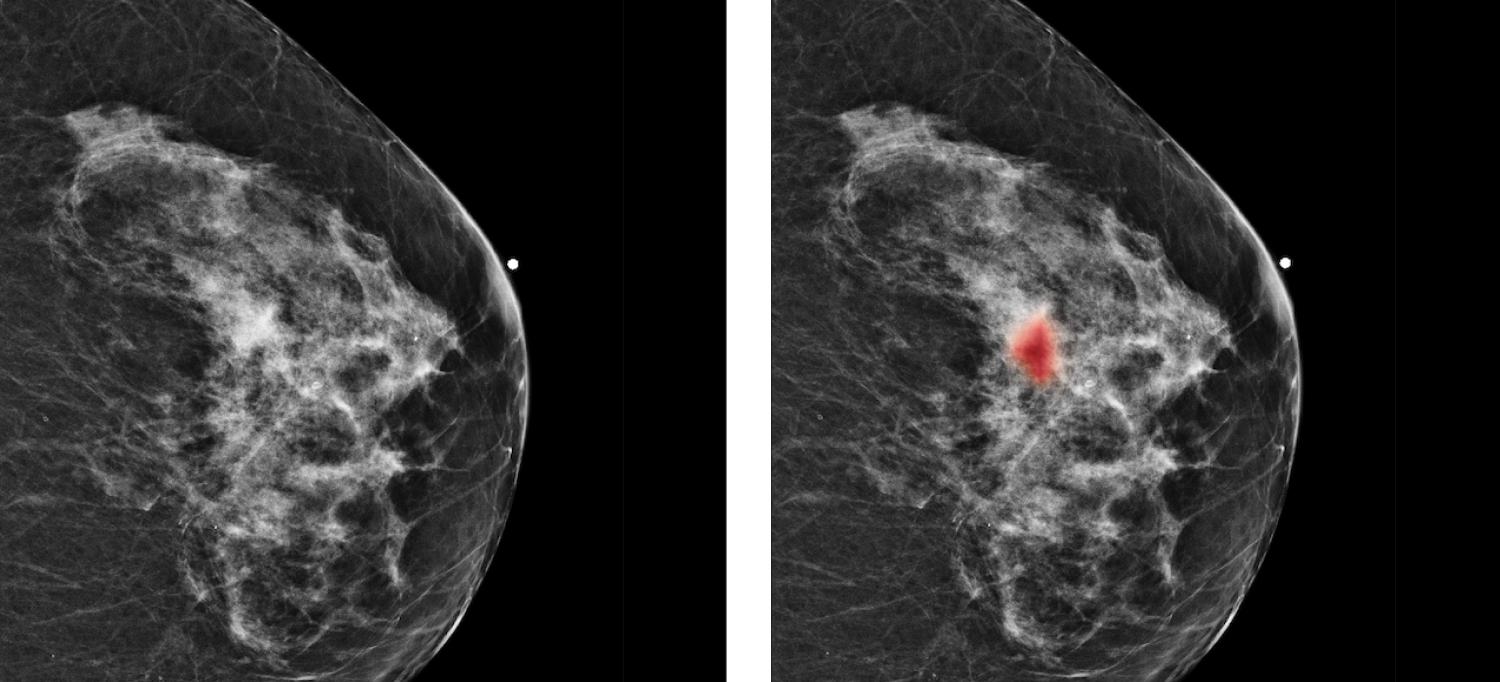

Radiologists missed a subtle mass on a mammography image (left). But it was identified by Perlmutter Cancer Center researchers using artificial intelligence (right, in red) as highly likely to be cancerous. A biopsy confirmed that the lesion was malignant.

Scan Courtesy Artie Shen

To train their system to differentiate between normal and suspicious tissue, the researchers fed it more than 2 million images drawn from mammograms performed at NYU Langone Health. “Like facial recognition software, our computers can examine—in a split second—features that are otherwise imperceptible,” notes Dr. Moy. They found that their artificial intelligence system has an accuracy rate of about 90 percent, compared to an overall average of 80 percent by radiologists. “Notably, when radiologists used this tool as a second reader, their performance improved,” says Dr. Moy. “So we want to reach that sweet spot where we use both.”